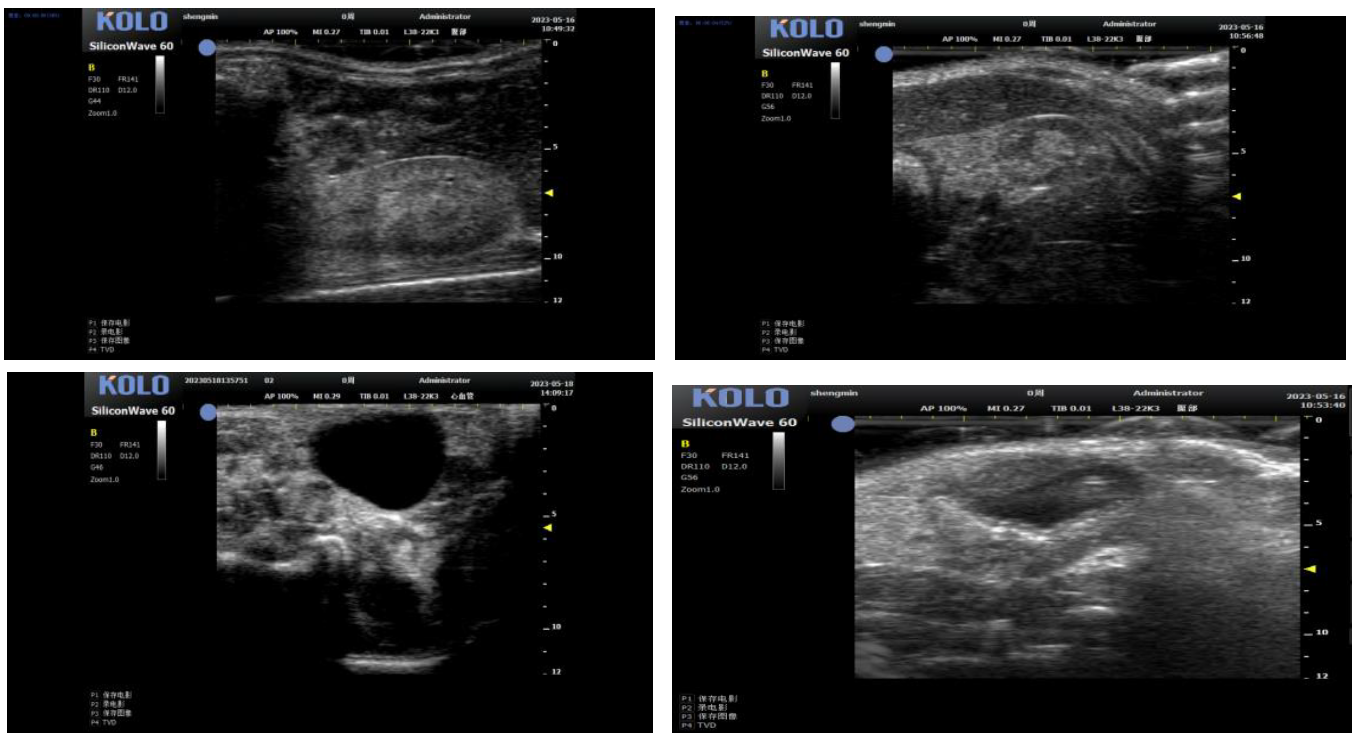

基于全球领先的CMUT 半导体超声技术,集成多项发明专利,珂纳医疗精心研发出 SiliconWave 60 超高频小动物超声成像系统。该系统微米级的超高清分辨率,8-62 MHz 超宽频段和丰富灵敏的彩色多普勒功能为临床前科研用户观察小动物的心血管、腹部脏 器、浅表组织及胚胎等提供了清晰多彩的超声图像。系统的实时无创操作也为科研实验 的反复验证,长期动态观察等提供了极大的便利性。

1. 小鼠心脏研究---左心室(长+短轴+M 超)

2. 小鼠心脏研究---四腔心(长轴+血流测速)

3、小鼠血管方面研究

3.1 腹主动脉(长+短轴+管壁距离测量+血流流速)

3.2 颈动脉(长轴)

4、内脏测量

5肿瘤测量(肿瘤大小精确测量)